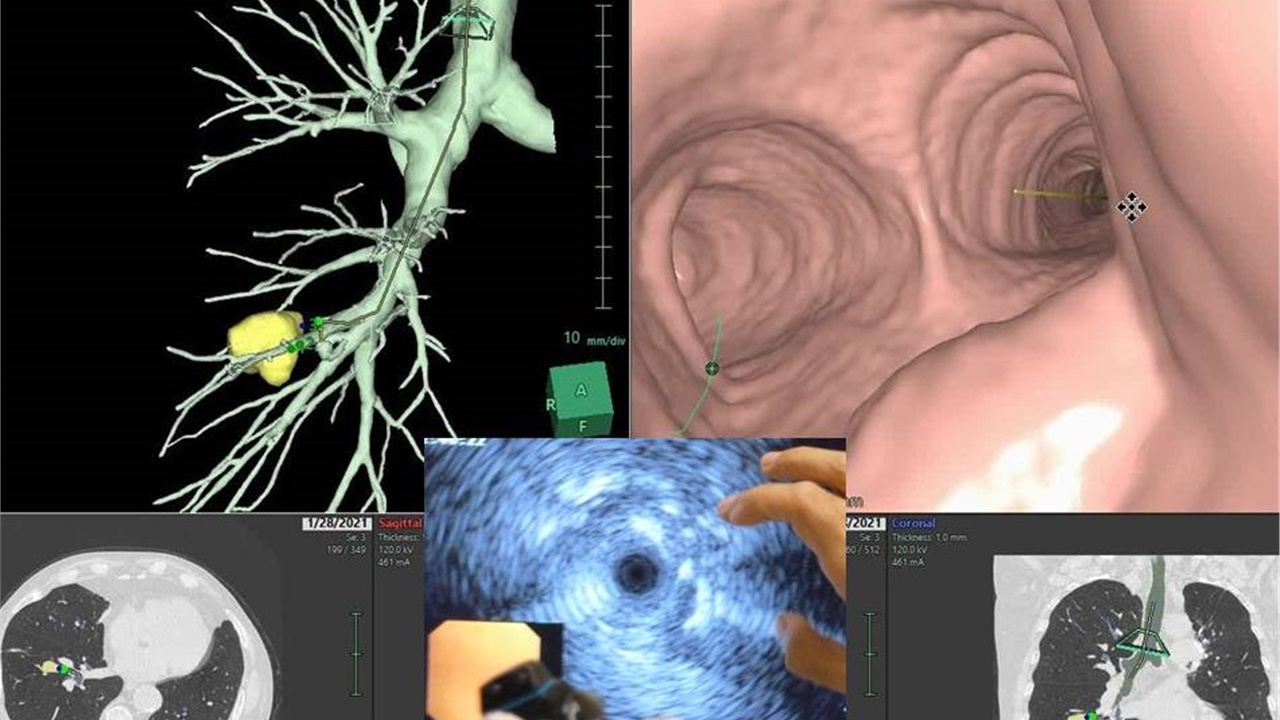

Bronchoscopy On Air #1: Peripheral Pulmonary Lesion / Rebiopsy

Whatch Live on 24 April 2021, 10:00 CEST. A video presentation of a case with peripheral pulmonary lesion approach for lung Ca. Followed by Live discussion by a group of experts....